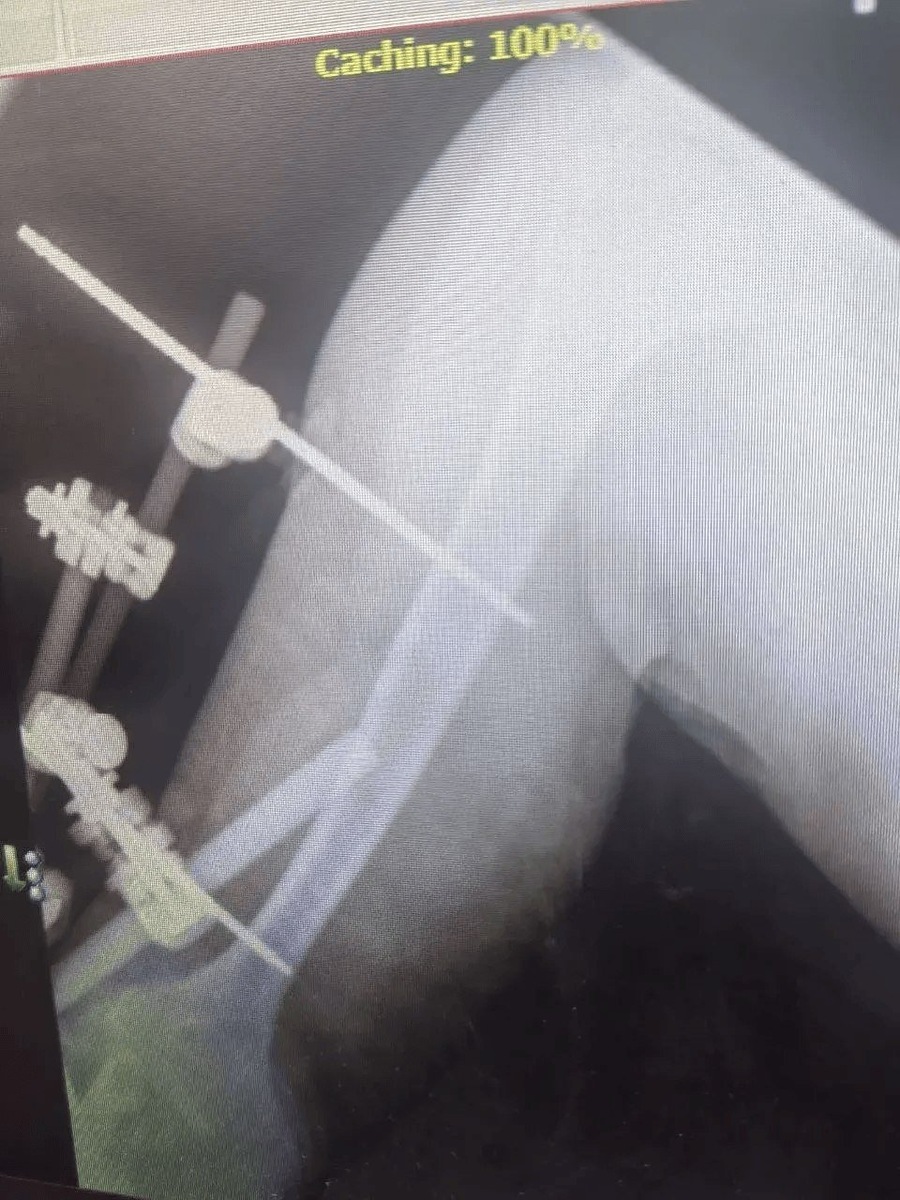

Ставропольские врачи спасли мужчину, упавшего с 6-метровой высоты. Пострадавшего доставили в городскую клиническую больницу скорой медицинской помощи с тяжёлой политравмой, сообщает пресс-служба минздрава Ставрополья. Мужчина 1972 года рождения получил множественные переломы и другие серьёзные травмы. Его лечением занималась команда специалистов разных профилей. Челюстно-лицевые хирурги провели шинирование, травматологи-ортопеды выполнили операцию на правой локтевой кости и восстановили левую лучевую. Также пациент проходил лечение у нейрохирургов и неврологов. "Течение посттравматического периода осложнилось токсическим гепатитом, но грамотная работа терапевта позволила справиться и с этим вызовом", — рассказали в минздраве региона. Благодаря слаженной работе врачей состояние мужчины стабилизировали. Его выписали, дальнейшее лечение он проходит амбулаторно под наблюдением специалистов.

Ставропольские врачи спасли мужчину, упавшего с 6-метровой высоты. Пострадавшего доставили в городскую клиническую больницу скорой медицинской помощи с тяжёлой политравмой, сообщает пресс-служба минздрава Ставрополья.

Мужчина 1972 года рождения получил множественные переломы и другие серьёзные травмы. Его лечением занималась команда специалистов разных профилей. Челюстно-лицевые хирурги провели шинирование, травматологи-ортопеды выполнили операцию на правой локтевой кости и восстановили левую лучевую. Также пациент проходил лечение у нейрохирургов и неврологов.